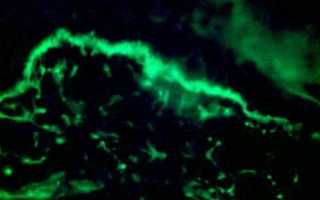

Обнаружение антител в крови осуществляется двумя основными методами. Первый из них — непрямая иммунофлуоресцентная микроскопия. При наличии антител они связываются с определёнными ядерными антигенами. В этом процессе используются флуоресцентные элементы, которые излучают свет в специфическом диапазоне. Благодаря микроскопии можно определить тип свечения.

Этот метод считается наиболее эффективным для выявления антинуклеарных антител и также известен как тест на волчаночные полосы.